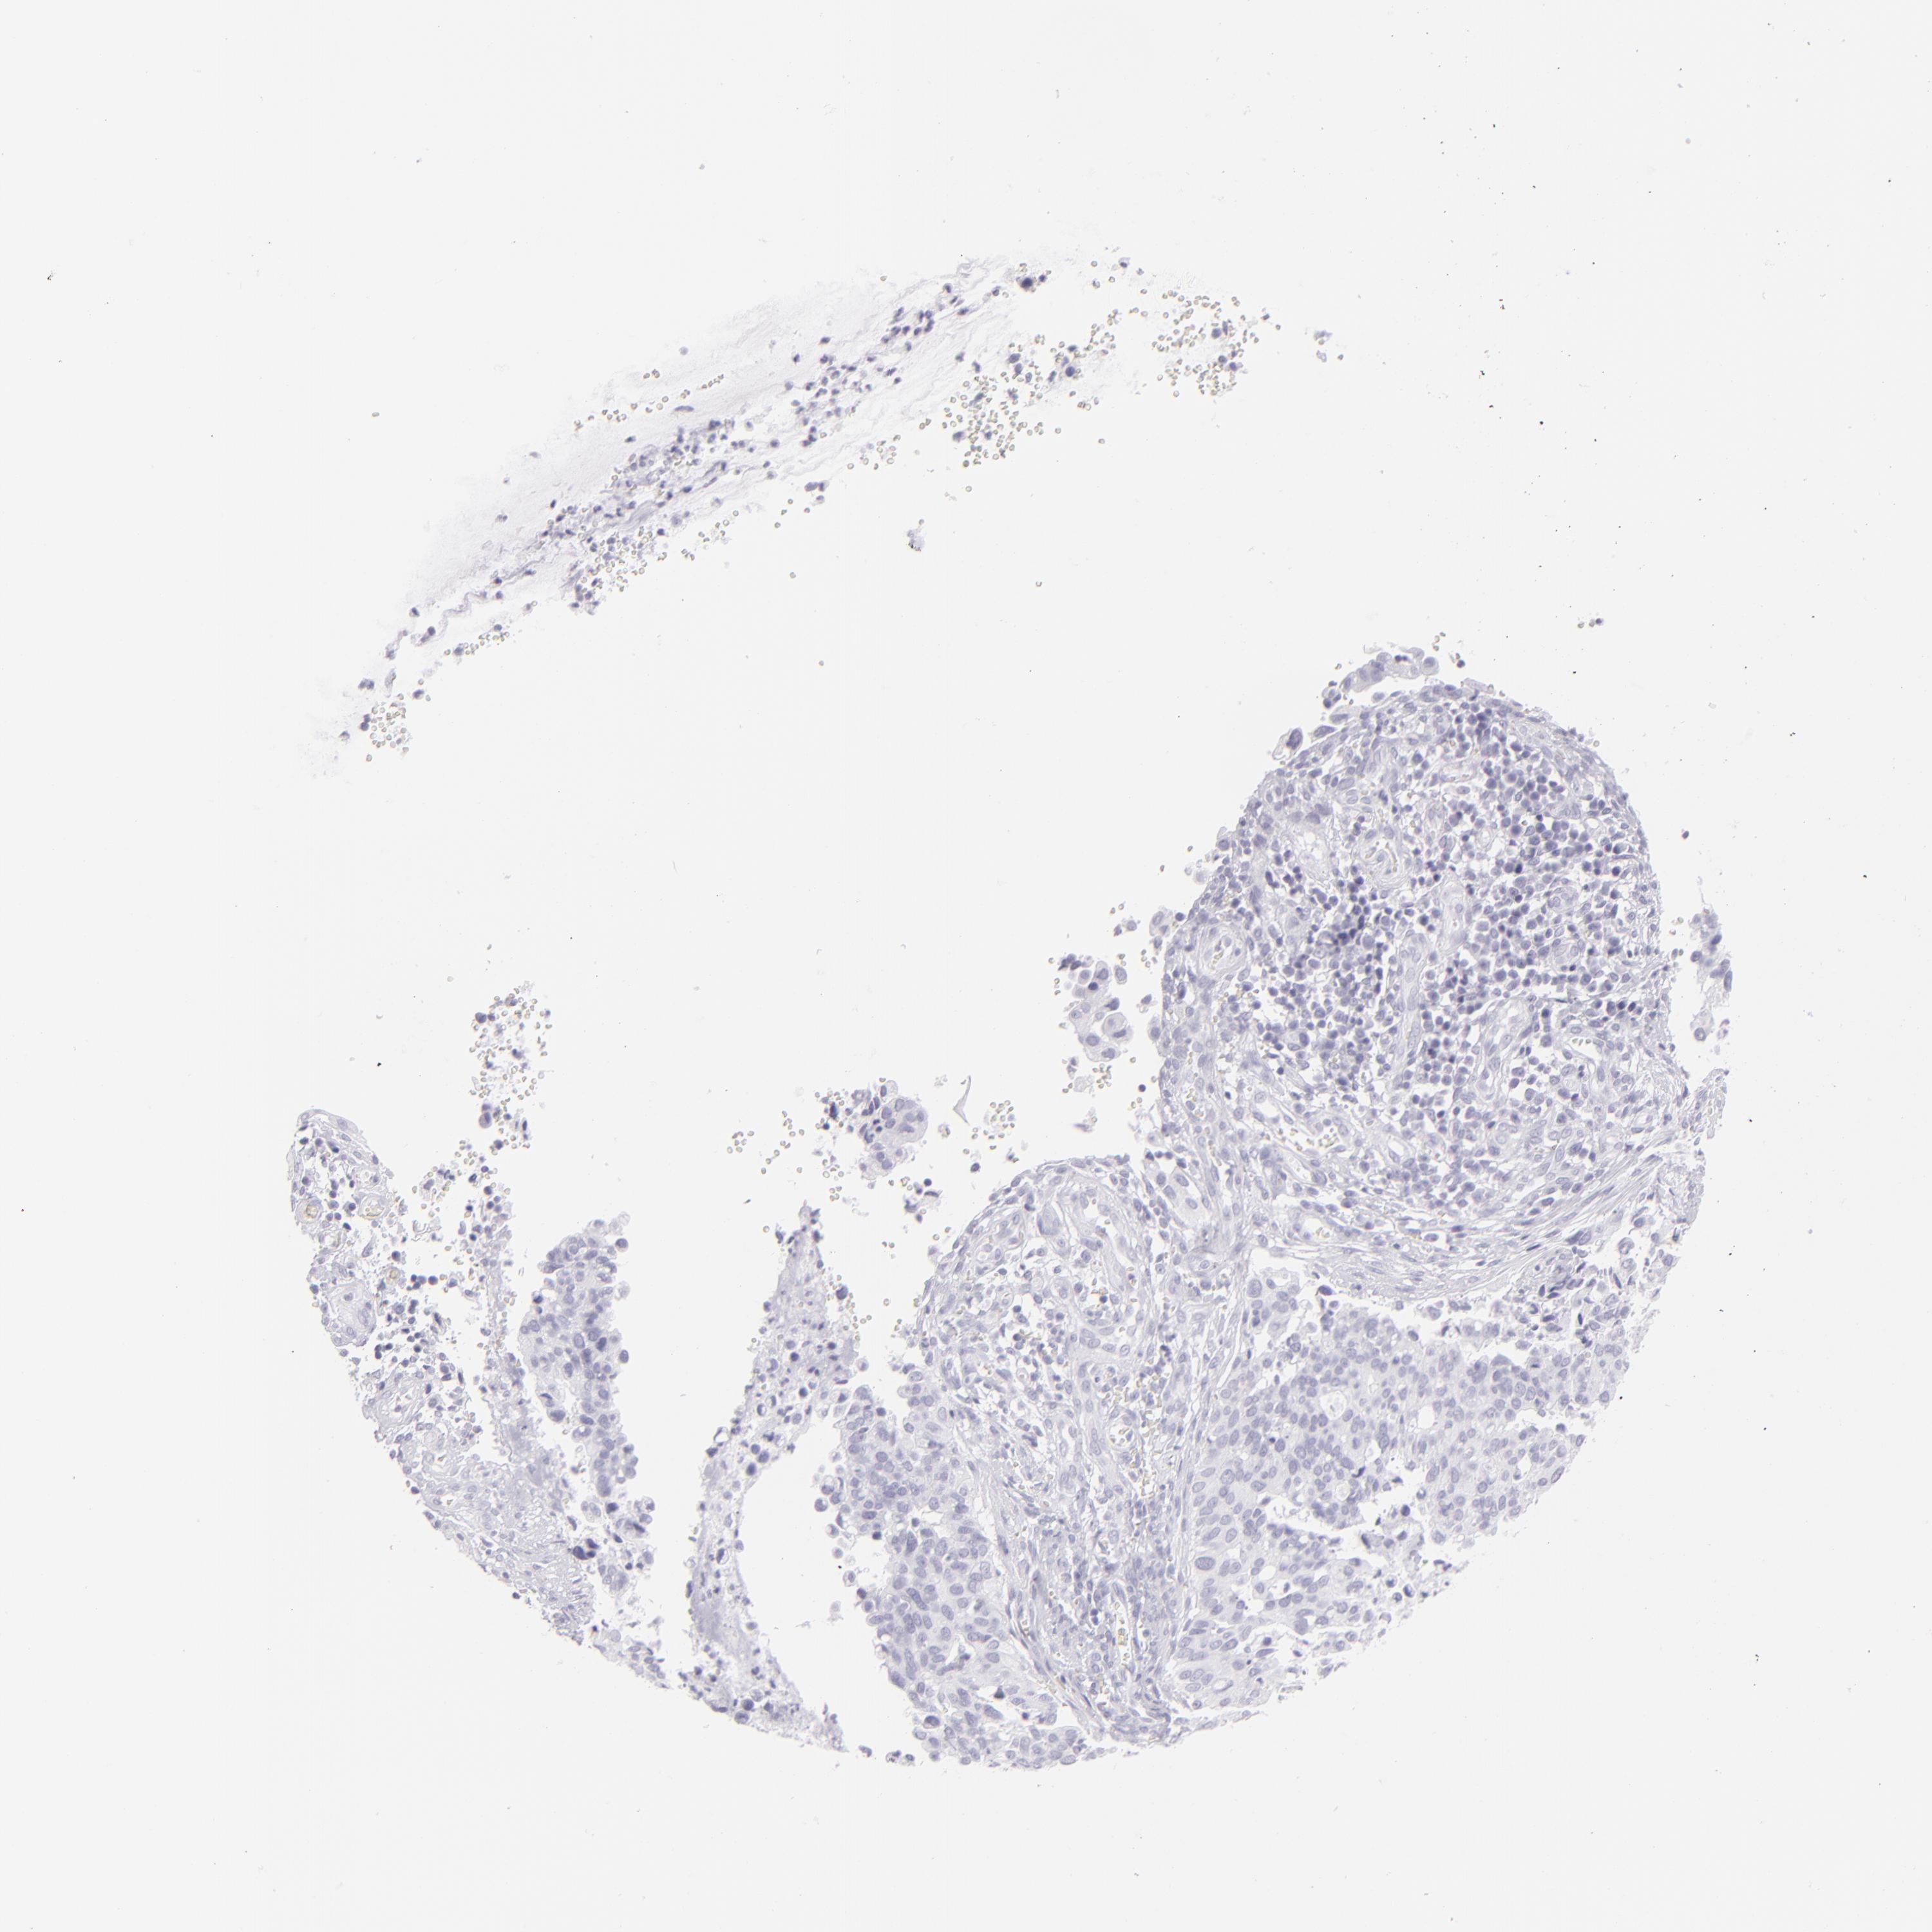

CERVICAL CANCER - Protein expressioni

A mouse-over function shows sample information and annotation data. Click on an image to view it in a full screen mode. Samples can be filtered based on level of antibody staining by selecting one or several of the following categories: high, medium, low and not detected. The assay and annotation is described here.

Note that samples used for immunohistochemistry by the Human Protein Atlas do not correspond to samples in the TCGA dataset.

Antibody stainingi

Antibody staining in the annotated cell types in the current human tissue is reported as not detected, low, medium, or high, based on conventional immunohistochemistry profiling in selected tissues. This score is based on the combination of the staining intensity and fraction of stained cells.

Each image is clickable and will lead to virtual microscopy that enables deeper exploration of all samples and also displays staining intensity scores, fraction scores and subcellular localization as well as patient and tissue information for each sample.

Antibody HPA030188

Antibody HPA030189

Antibody CAB002210

Squamous cell carcinoma, NOS

Adenocarcinoma, NOS